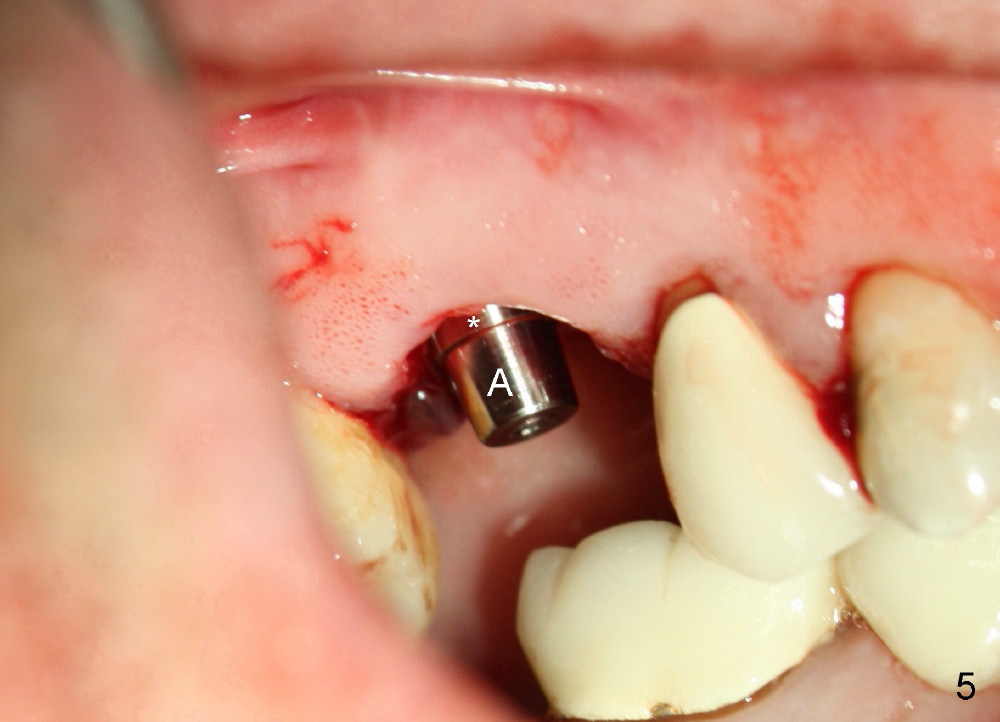

A 51-year-old man requests taking care of hemorrhage and odor associated with the tooth #3 (Fig.1). Due to religious and financial issues, the neighboring teeth will be treated later (supraeruption of #2 (arrow) and periapical radiolucency of #4 (*)). CBCT reveals that the septum of #3 is large enough to hold 4.5 mm implant (Fig.2). In fact osteotomy is created as planned in the septum using drills and taps (Fig.3 after removing 4.5x20 mm tap). Primary stability is obtained with a 4.5x20 mm implant (> 60 Ncm, Fig.4). The gap (*) is bone grafted; an abutment is placed (Fig.5 A); an immediate provisional is fabricated and cemented to cover the socket (Fig.6 P). When the socket heals in 3 weeks postop, the provisional and the abutment are removed for easy oral hygiene. Bone regenerates around the implant 3.5 months postop (Fig.7 *), but the 2nd molar has shifted mesially (arrow), presenting a restoration challenge.